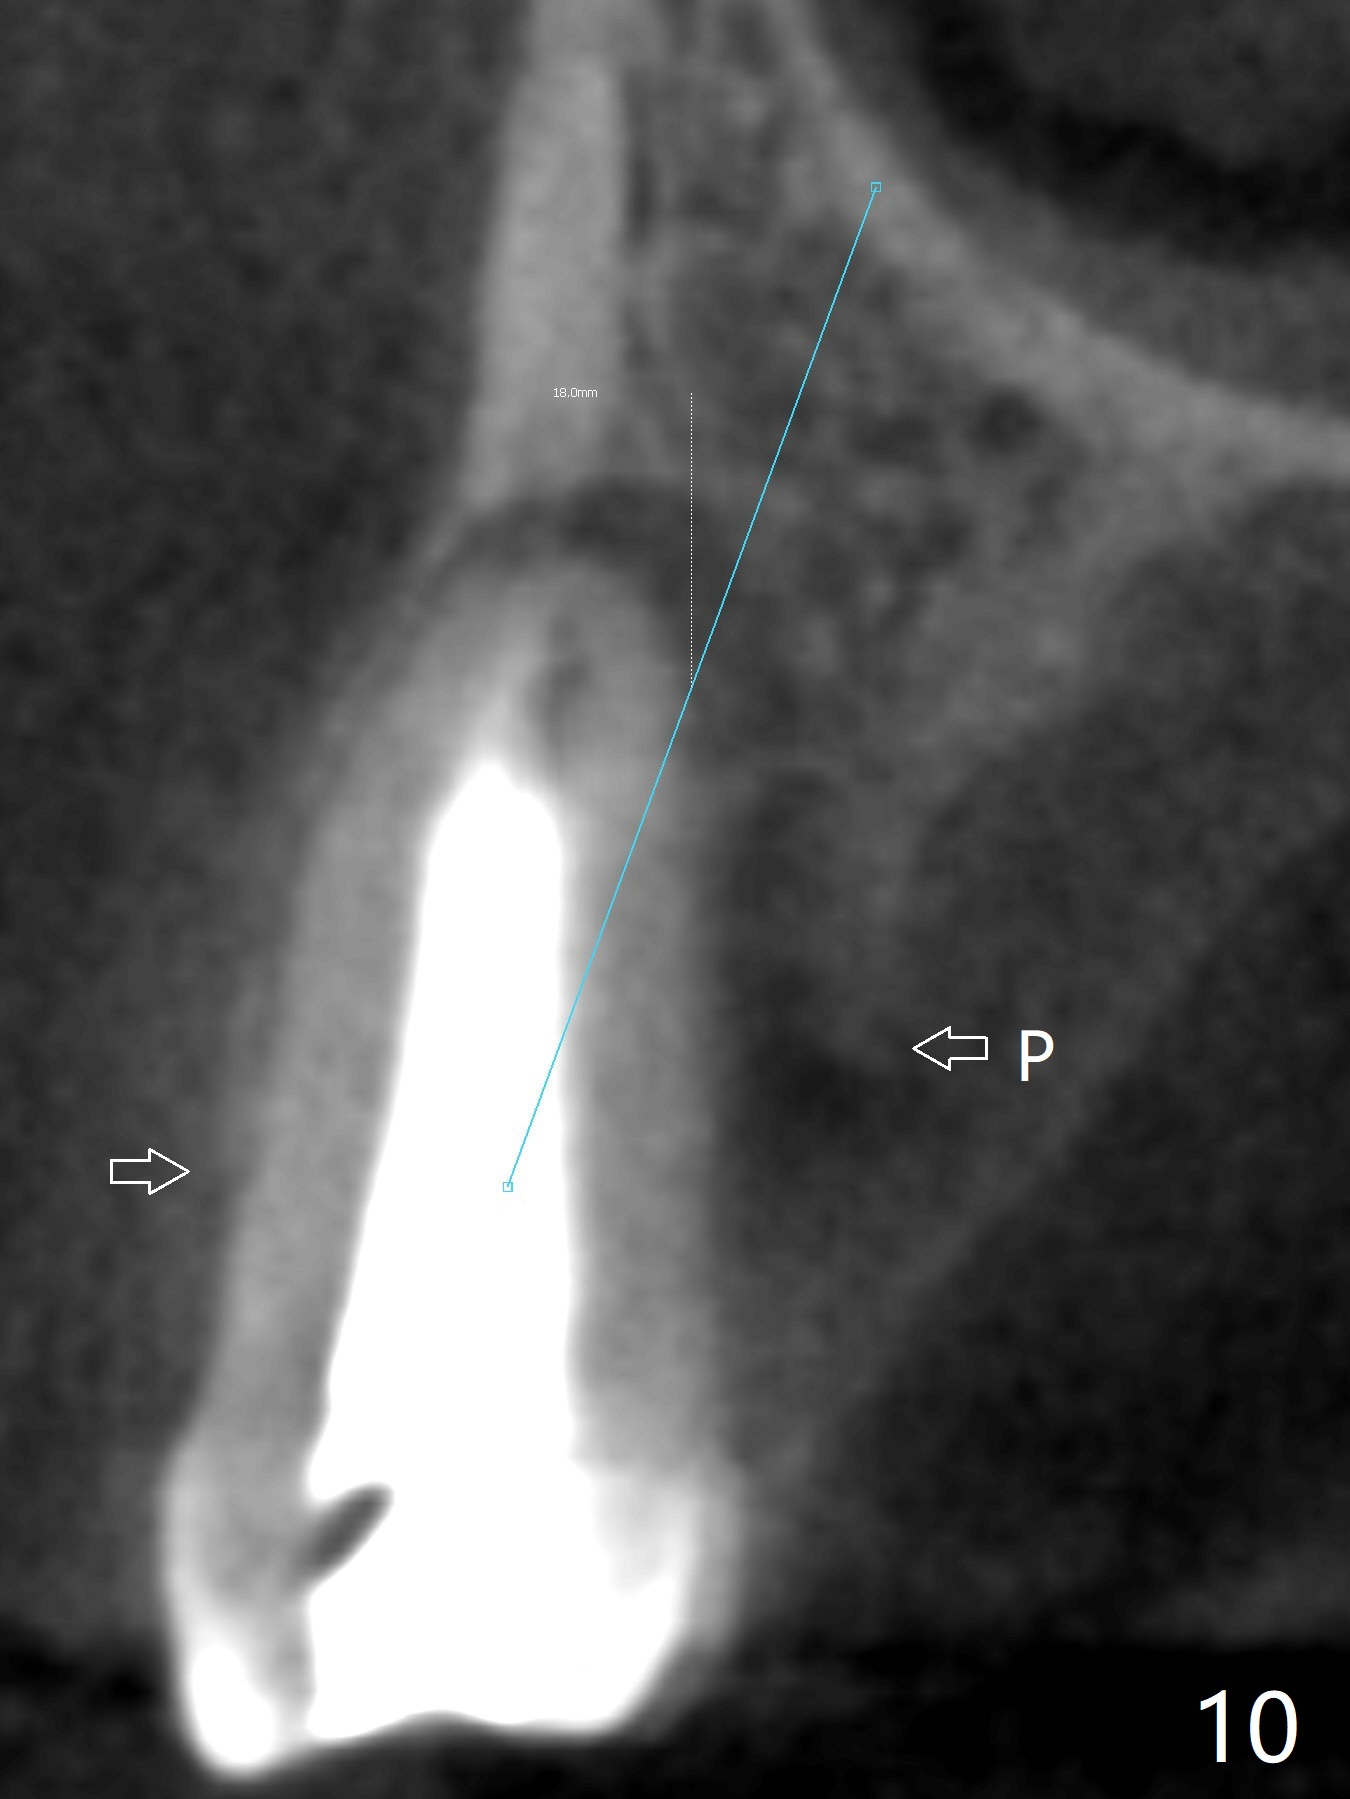

In fact there is a small buccal fistula, which is communicated with the underlying implant threads. Although preop CT shows that the buccal crest is lower than the palatal (3.8x13 mm, Fig.10 P) one, intraop finding of missing buccal plate should dictate a shorter implant (Fig.11) or onlay graft to avoid periimplantitis. Regeneration of the bone plate is limited. Later the fistula disappears with formation of a concavity (Fig.13). There is no symptom. Is bone graft necessary with a remote incision? 3-D images of CT taken 1 year 5 months post cementation show possible mesiobuccal and distopalatal bony defects (Fig.13-16). It is possible that bone graft was placed enough palatal (Fig.16). DO composite at #3 is redo satisfactorily (Fig.17 *).